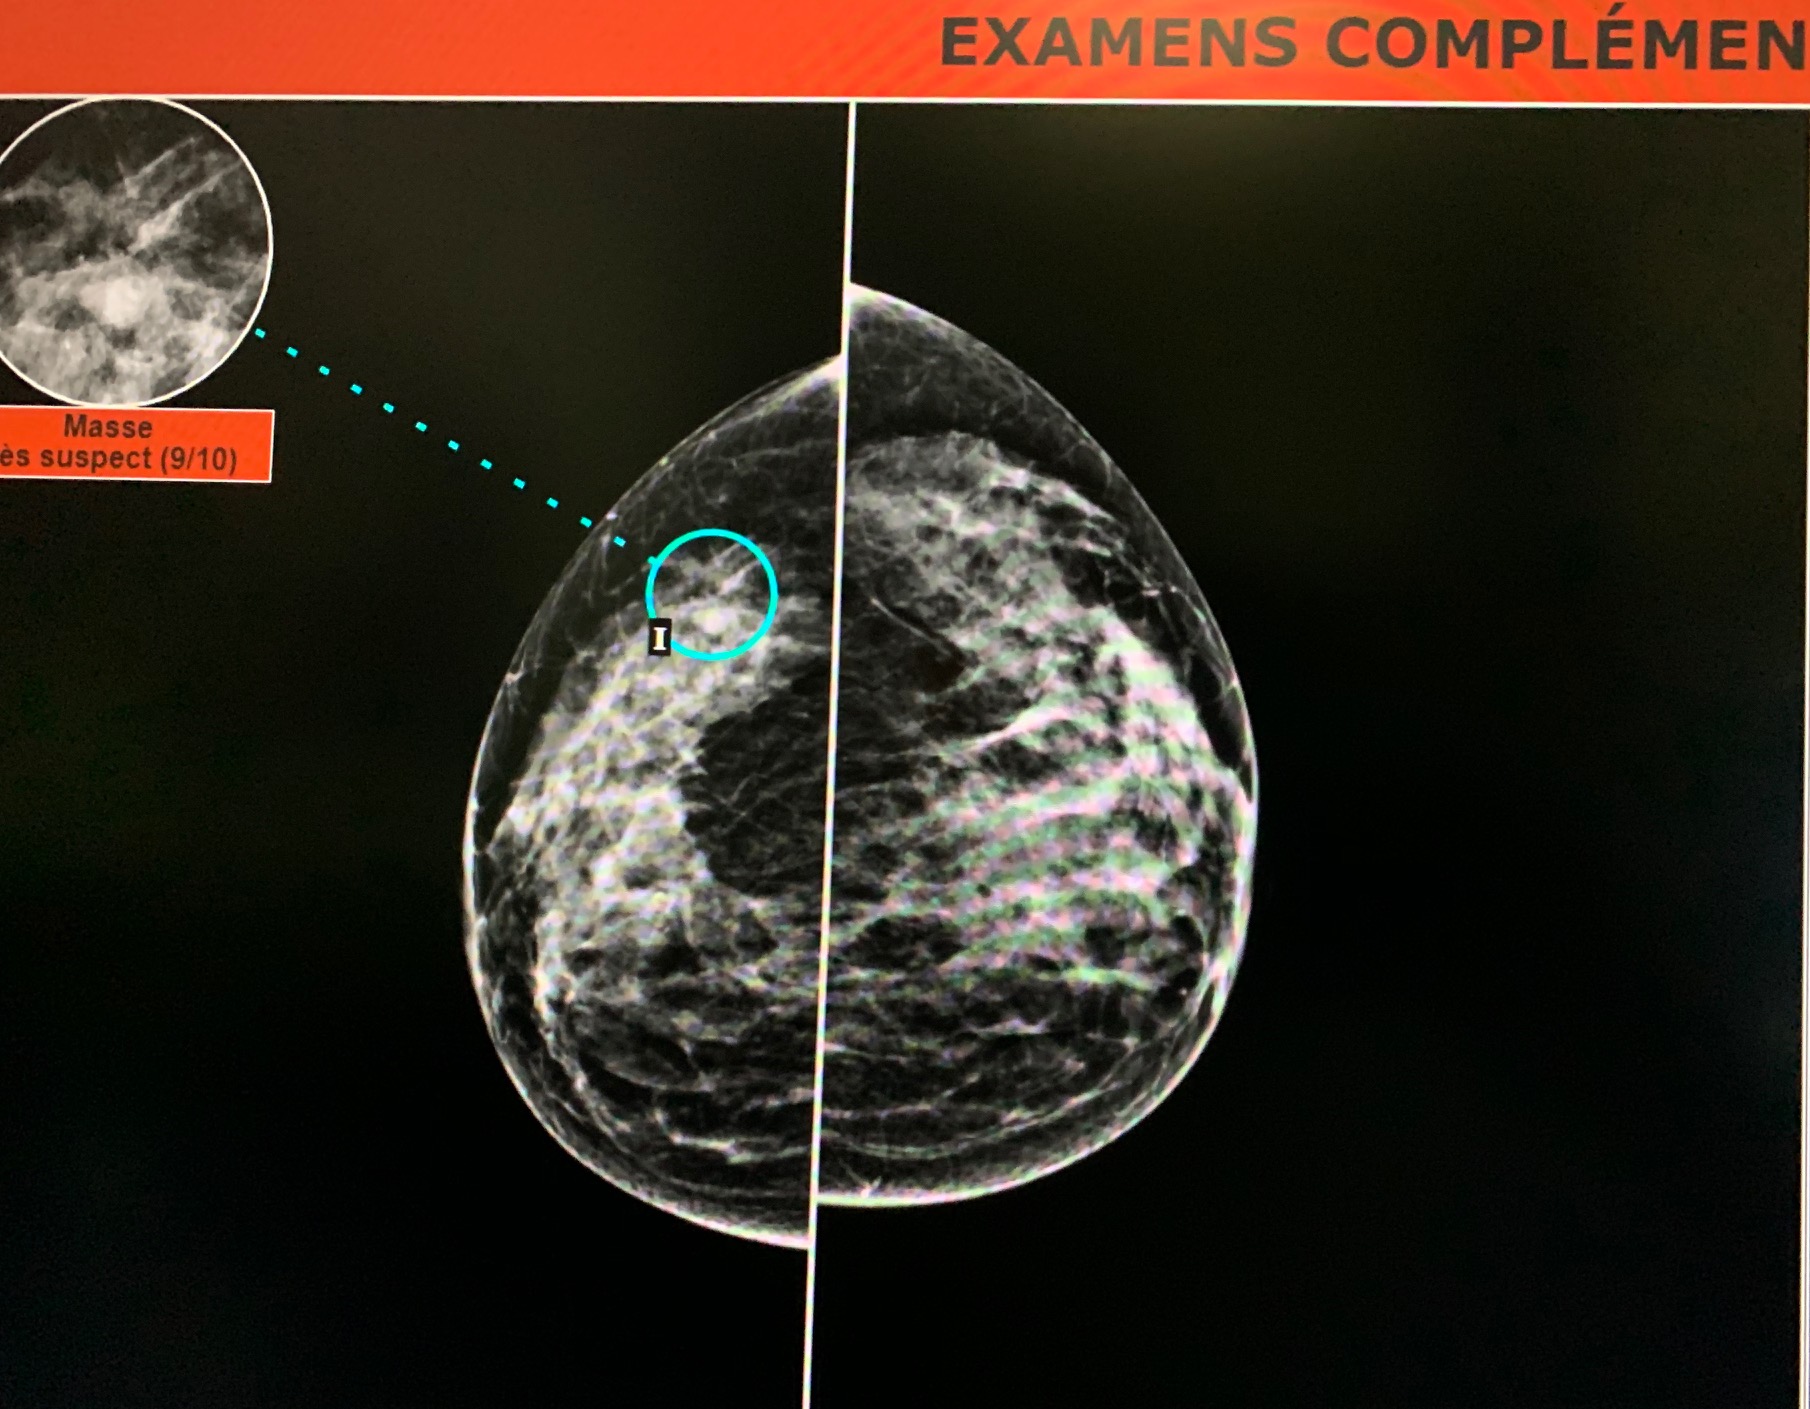

En examinant l’analyse du logiciel d’IA Mammoscreen™ j’ai vu que le logiciel a pointé une zone rétromamelonnaire externe.

Comme Mammoscreen™ a mis en rouge, je me suis dit que par prudence je devais persévérer et j’ai donc complété par une échographie qui a mis en évidence une image hypoéchogène à contours irréguliers avec des zones de rigidité à l’étude elastographique, situé à l’union des quadrants externes du sein gauche.

L’échographie montre une masse hypoéchogène a contours irréguliers avec rigidité élastographique.